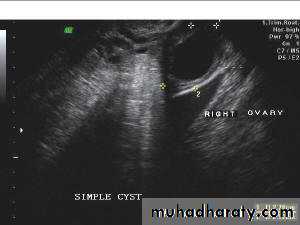

Rt. ovarian simple cyst:

Ultrasonography in Gynaecology